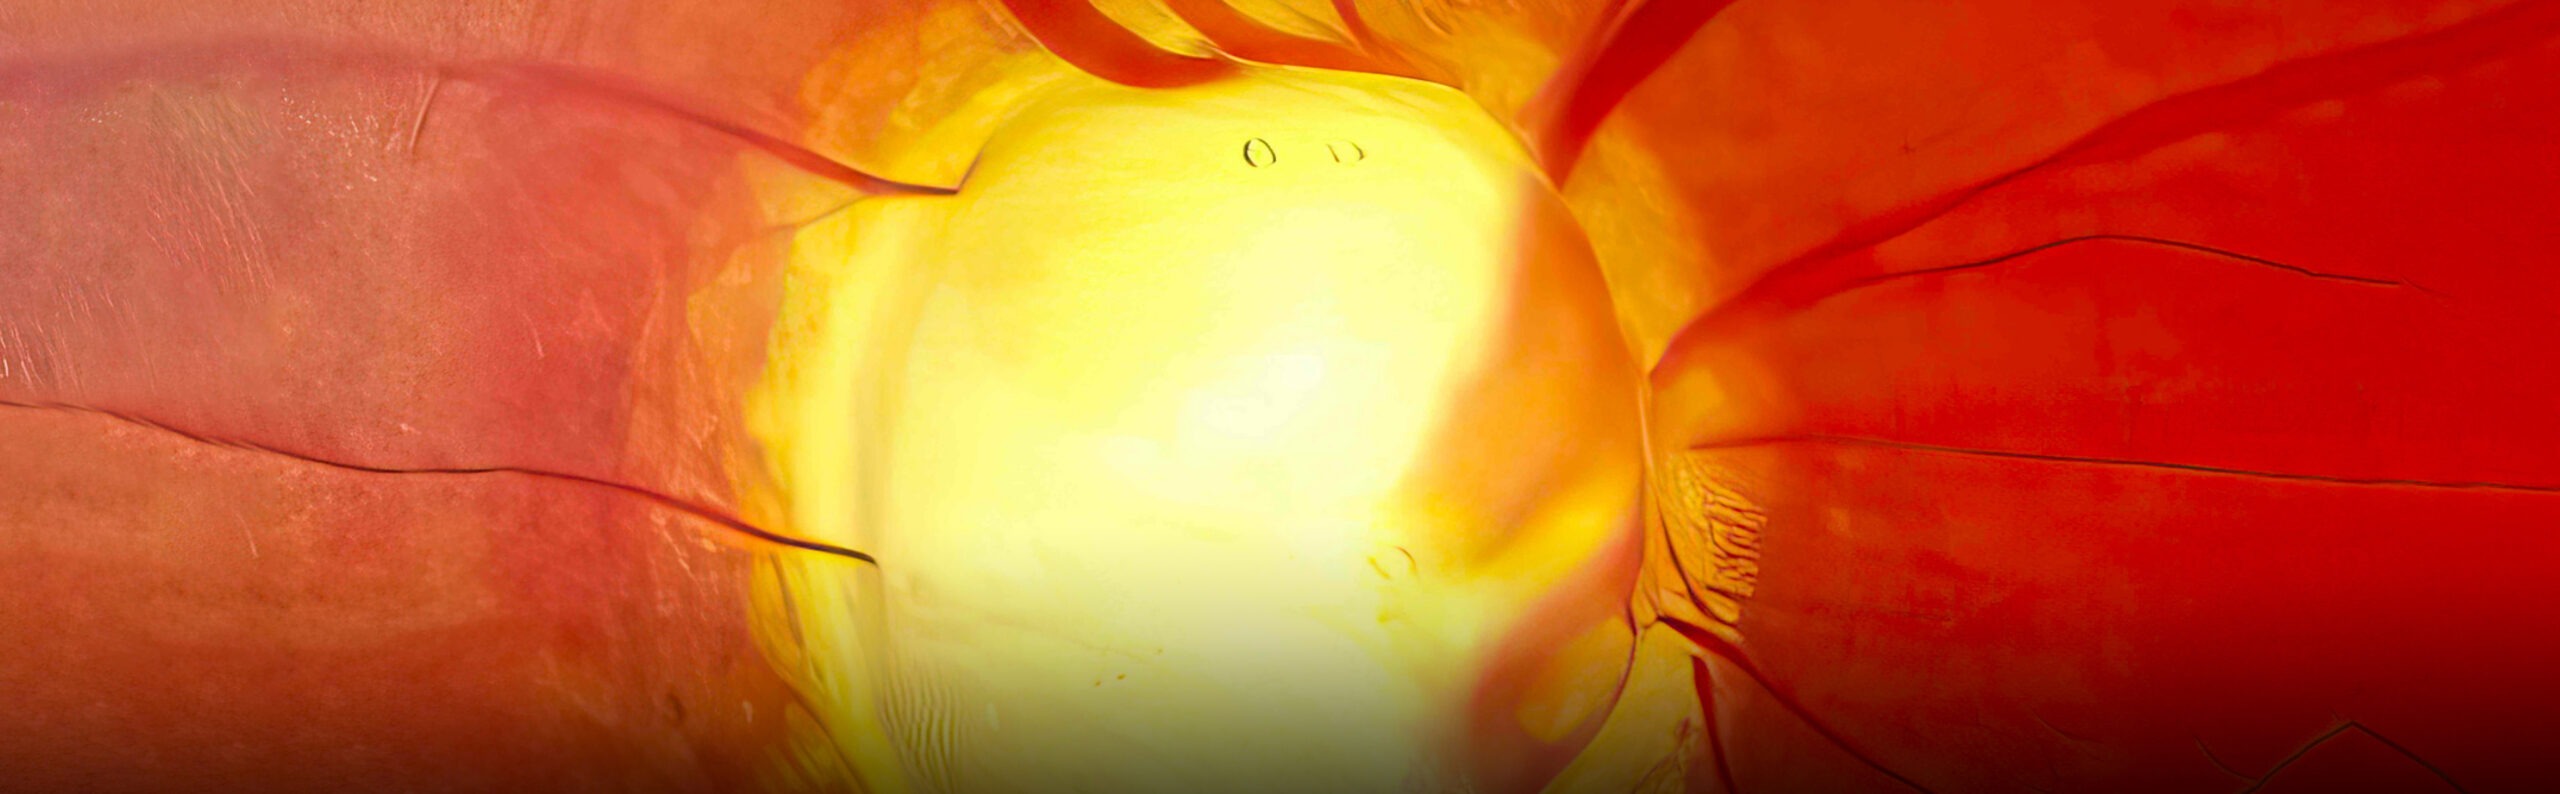

The optic nerves behind your eyes transmit signals from your retina to your brain, making them essential for clear vision. Glaucoma encompasses degenerative eye conditions that damage the optic nerve, often due to abnormally high pressure in one or both eyes. This pressure leads to irreversible vision loss over time.

Diagnosis begins with a thorough examination, including a visual field test for peripheral vision loss and an optical coherence tomography (OCT) imaging test to assess retinal damage. Eye pressure tests are also standard.